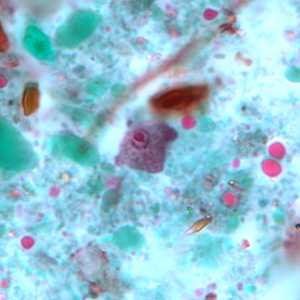

E. polecki cysts stained with trichrome.

Figure A: Cyst of E. polecki stained with trichrome. Notice the large nucleus with a pleomorphic karyosome and numerous variably-shaped chromatoid bodies.

Figure B: Cyst of E. polecki stained with trichrome. Notice the large nucleus with a pleomorphic karyosome and numerous variably-shaped chromatoid bodies.

Figure C: Cyst of E. polecki stained with trichrome. Notice the large nucleus with a pleomorphic karyosome and numerous variably-shaped chromatoid bodies.

Figure D: Cyst of E. polecki stained with trichrome. Notice the large nucleus with a pleomorphic karyosome and numerous variably-shaped chromatoid bodies.

Figure E: Cyst of E. polecki stained with trichrome. Notice the large nucleus with a pleomorphic karyosome and numerous variably-shaped chromatoid bodies.

Figure F: Cyst of E. polecki stained with trichrome. Notice the large nucleus with a pleomorphic karyosome and numerous variably-shaped chromatoid bodies.